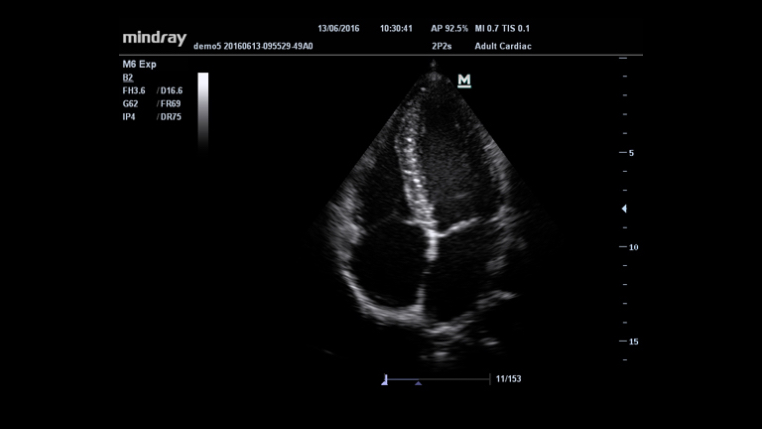

???? ?? ??? ?? ?? ??? ??? ?? ?? ?? ???? ???? ?? ????? ?? ??? ??? ?????. ??? ???? ??? ???? ?? ??? ?? ??? ?? ?? ??? ?? ???? ?? ?????? ??? M6? ??????, ? ???? ?? ? ?? ?? ??? ???? ??? ??? ??? ?? ???? ???? ?????.